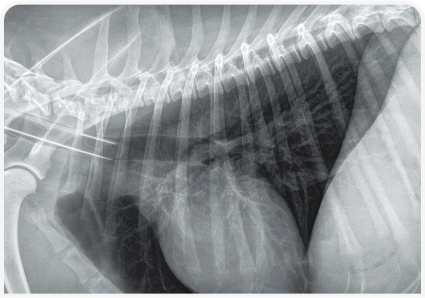

Рентгенография позволяет определить размеры, форму, положение, непрозрачность и края печени, а также обнаружить скопления газа или минерализацию (Рисунок 2). Ультразвуковое исследование помогает определить распространенность поражения печени (очаговое, многоочаговое или диффузное), а также оценить степень васкуляризации и облегчить получение образцов (для цитологического и культурального исследований и биопсии) (Рисунок 3). Однако следует помнить, что отсутствие патологических изменений при ультразвуковом исследовании не всегда свидетельствует о здоровье печени.